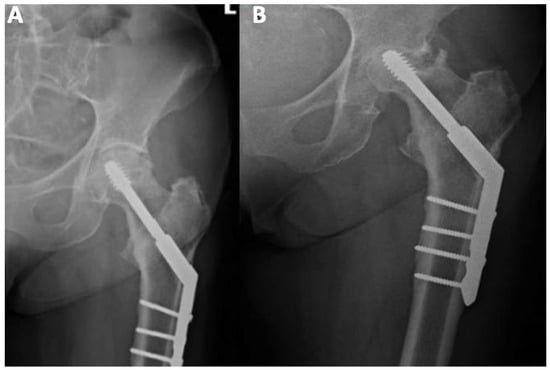

Total hip arthroplasty (THA) should be performed in patients with a significant femoral head collapse, loss of hip function, and severe pain. The procedure involves the removal of the ball and socket of the hip and replacement with an artificial implant (Figure 4). THA is a suboptimal choice for young patients due to activity restriction and possible future revision of the implant [63]. Most patients, however, have good outcomes after THA, particularly pain relief and restoring hip function [48,72].

Figure 4. Arthroplasty of the left hip due to avascular necrosis of the femoral head.